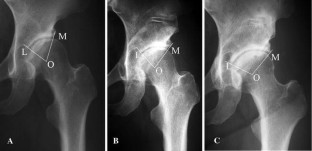

Twenty-one women (21 joints) who had undergone RAO with multiple drillings at acetabular fossa (group D) were included. As a control group, 12 women (14 joints) without drillings in RAO procedure were observed (group C). The center-edge angle (CE angle), acetabular roof obliquity (AC angle), head lateralization index (HLI), and the angle between medial and lateral edge of acetabular roof (LOM angle) were measured on the radiographs preoperatively, at 1 month, 2 years postoperatively, and at the last follow-up.

Fig. 2